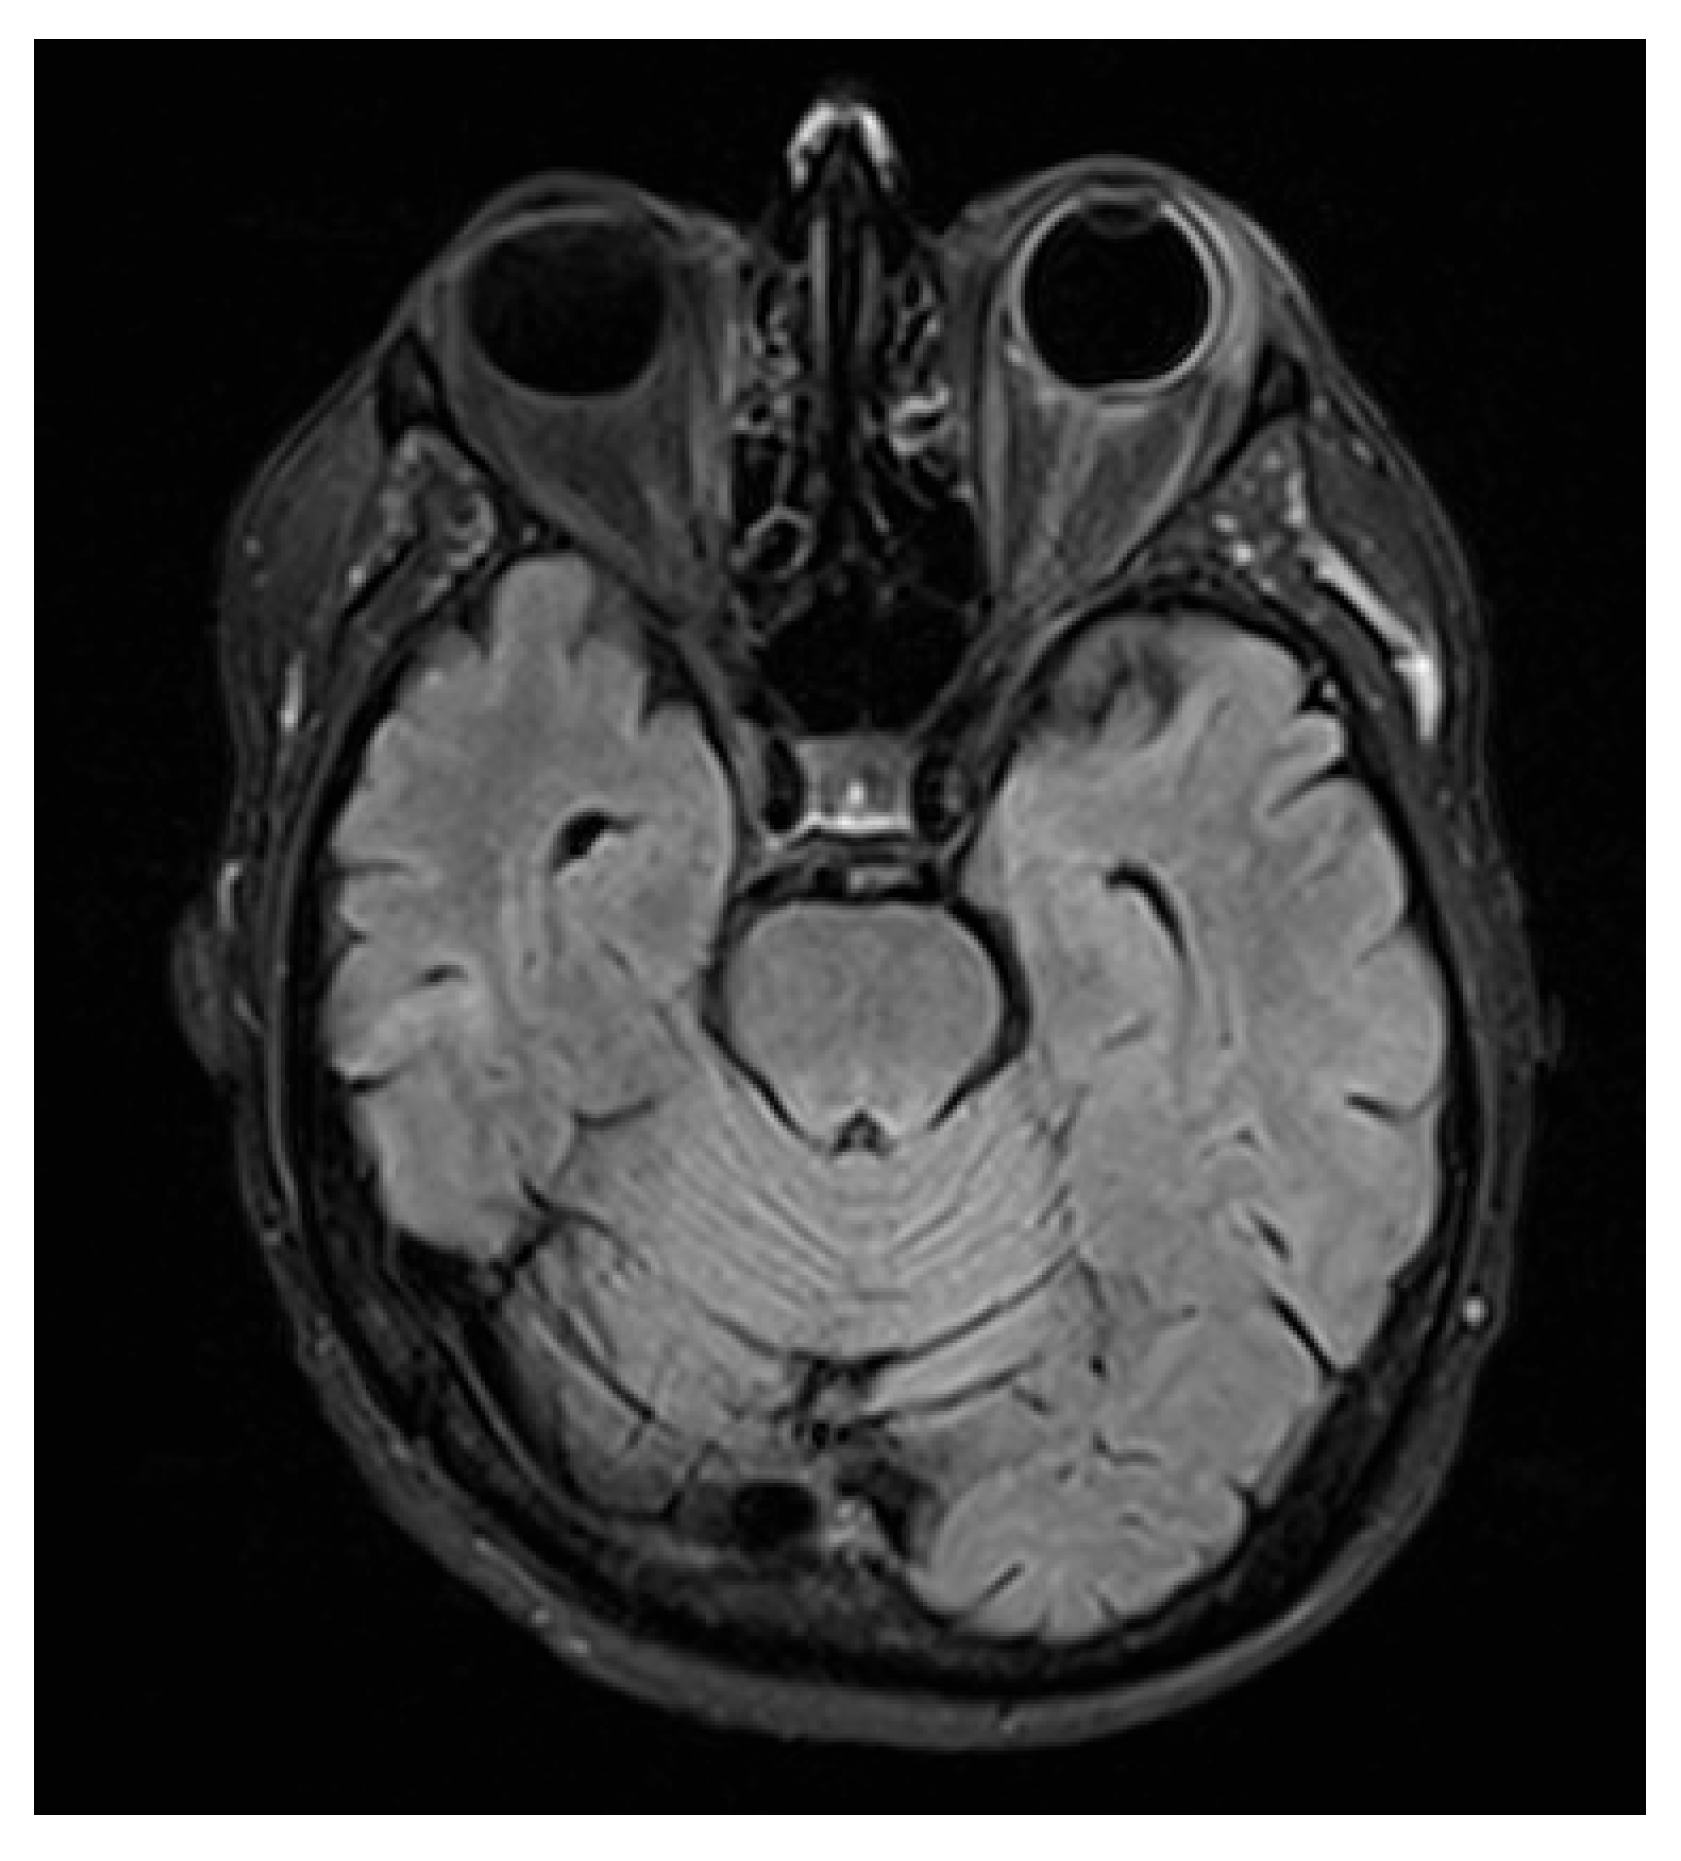

The ophthalmic manifestations of leukemia can be classified into two main categories: primary (direct) involvement, due to infiltration of neoplastic cells such as leukemic infiltrates; and secondary (indirect) involvement, from dysregulated hematopoiesis or chemotherapy, causing cytopenias (anemia, thrombocytopenia), hyperviscosity, and immunosuppression with opportunistic infections [8]. These ocular findings occur across acute and chronic leukemias, both myeloid and lymphoblastic. Because they arise at different disease stages and via distinct mechanisms, we will discuss them separately.

Orbital involvement may arise post-remission or because of therapy or GVHD. Immunocompromised patients are prone to opportunistic infections. Lacrimal gland infiltration by leukemia, GVHD, or radiation commonly causes severe dry eye with potential corneal complications [49,58]. Infectious processes such as cellulitis or dacryocystitis require prompt antibiotic and chemotherapy management [59] (Figure 4).

Figure 4. Ocular involvement in leukemia: (a) primary (direct) infiltration and (b) secondary (indirect or treatment-related) alterations [60].